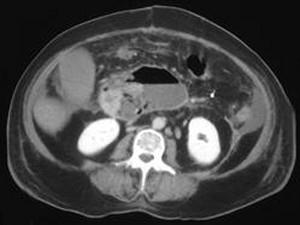

问题 女,33岁,发热,中上腹压痛反跳痛,血清淀粉酶增高,CT检查如图,最可能的诊断是 ( )

选项 A、胰腺假性囊肿 B、胰腺癌 C、慢性胰腺炎 D、胰腺脓肿 E、急性胰腺炎

答案 D